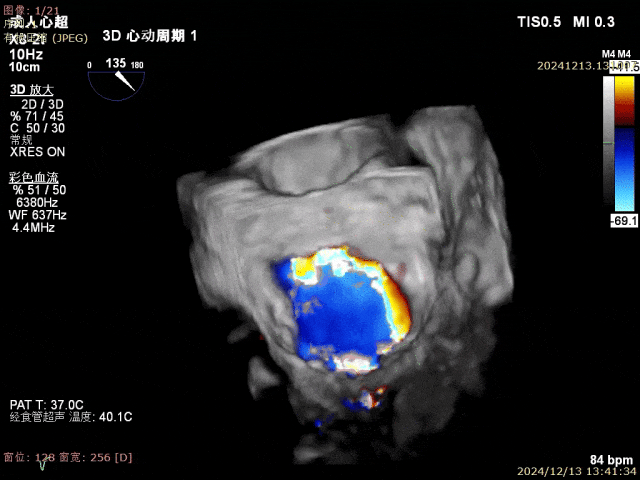

患者为68岁男性,3月前出现气短,活动后明显,休息可缓解,无明显胸痛,无夜间呼吸困难,就诊当地医院考虑“肺炎、心衰”,给予对症治疗好转,具体不详,无明显发热,无咳嗽咳痰,出院后未规律服药。10天前,气短再发,就诊当地医院心脏彩超提示二尖瓣后叶腱索断裂,二尖瓣关闭不全伴重度反流。左心增大,室间隔增厚,肺动脉高压,三尖瓣轻度反流,主动脉瓣中度反流。心电图提示房颤,左室肥大。为进一步诊治入院。经食道超声提示:患者二尖瓣后叶脱垂伴腱索断裂,前叶2.6cm,后叶1.4cm,脱垂宽度16mm,脱垂高度8mm,瓣口面积6.0cm²。

术前影像